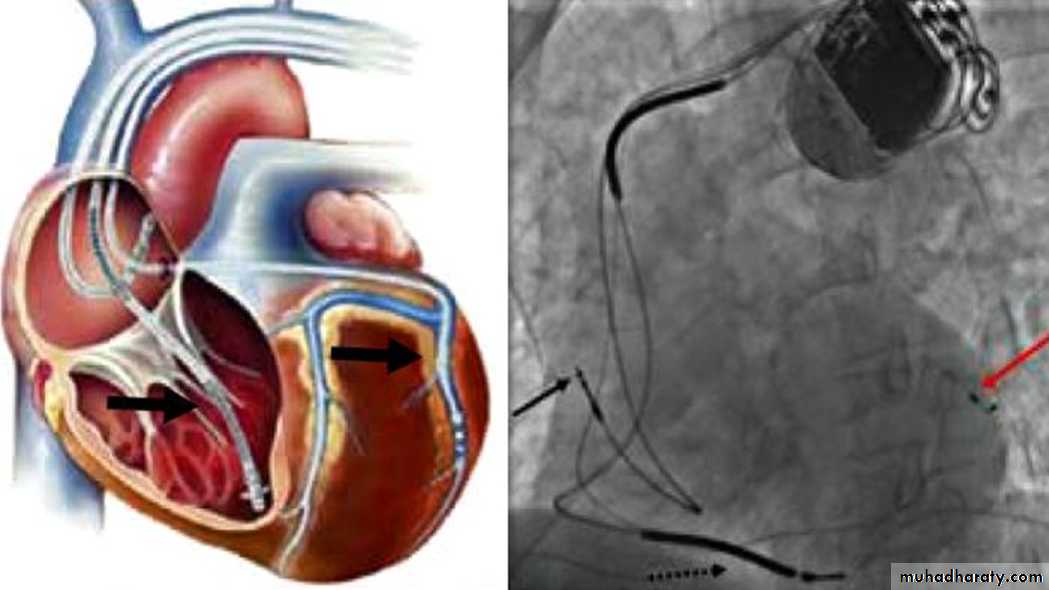

Implantable Cardioverter-Defibrillators for HF( ICD) –CRT

Sustained ventricular tachycardia is associated with sudden cardiac death in HF.

About one-third of mortality in HF is due to sudden cardiac death.Patients with ischemic or nonischemic cardiomyopathy, NYHA class II to III HF, and LVEF ≤ 35% have a significant survival benefit from an implantable cardioverter-defibrillator (ICD) for the primary prevention of SCD.

Cardiac-Resynchronization-Therapy

Mechanical circulatory support:

Intraaortic balloon pumpLeft ventricular assist device (LVAD).